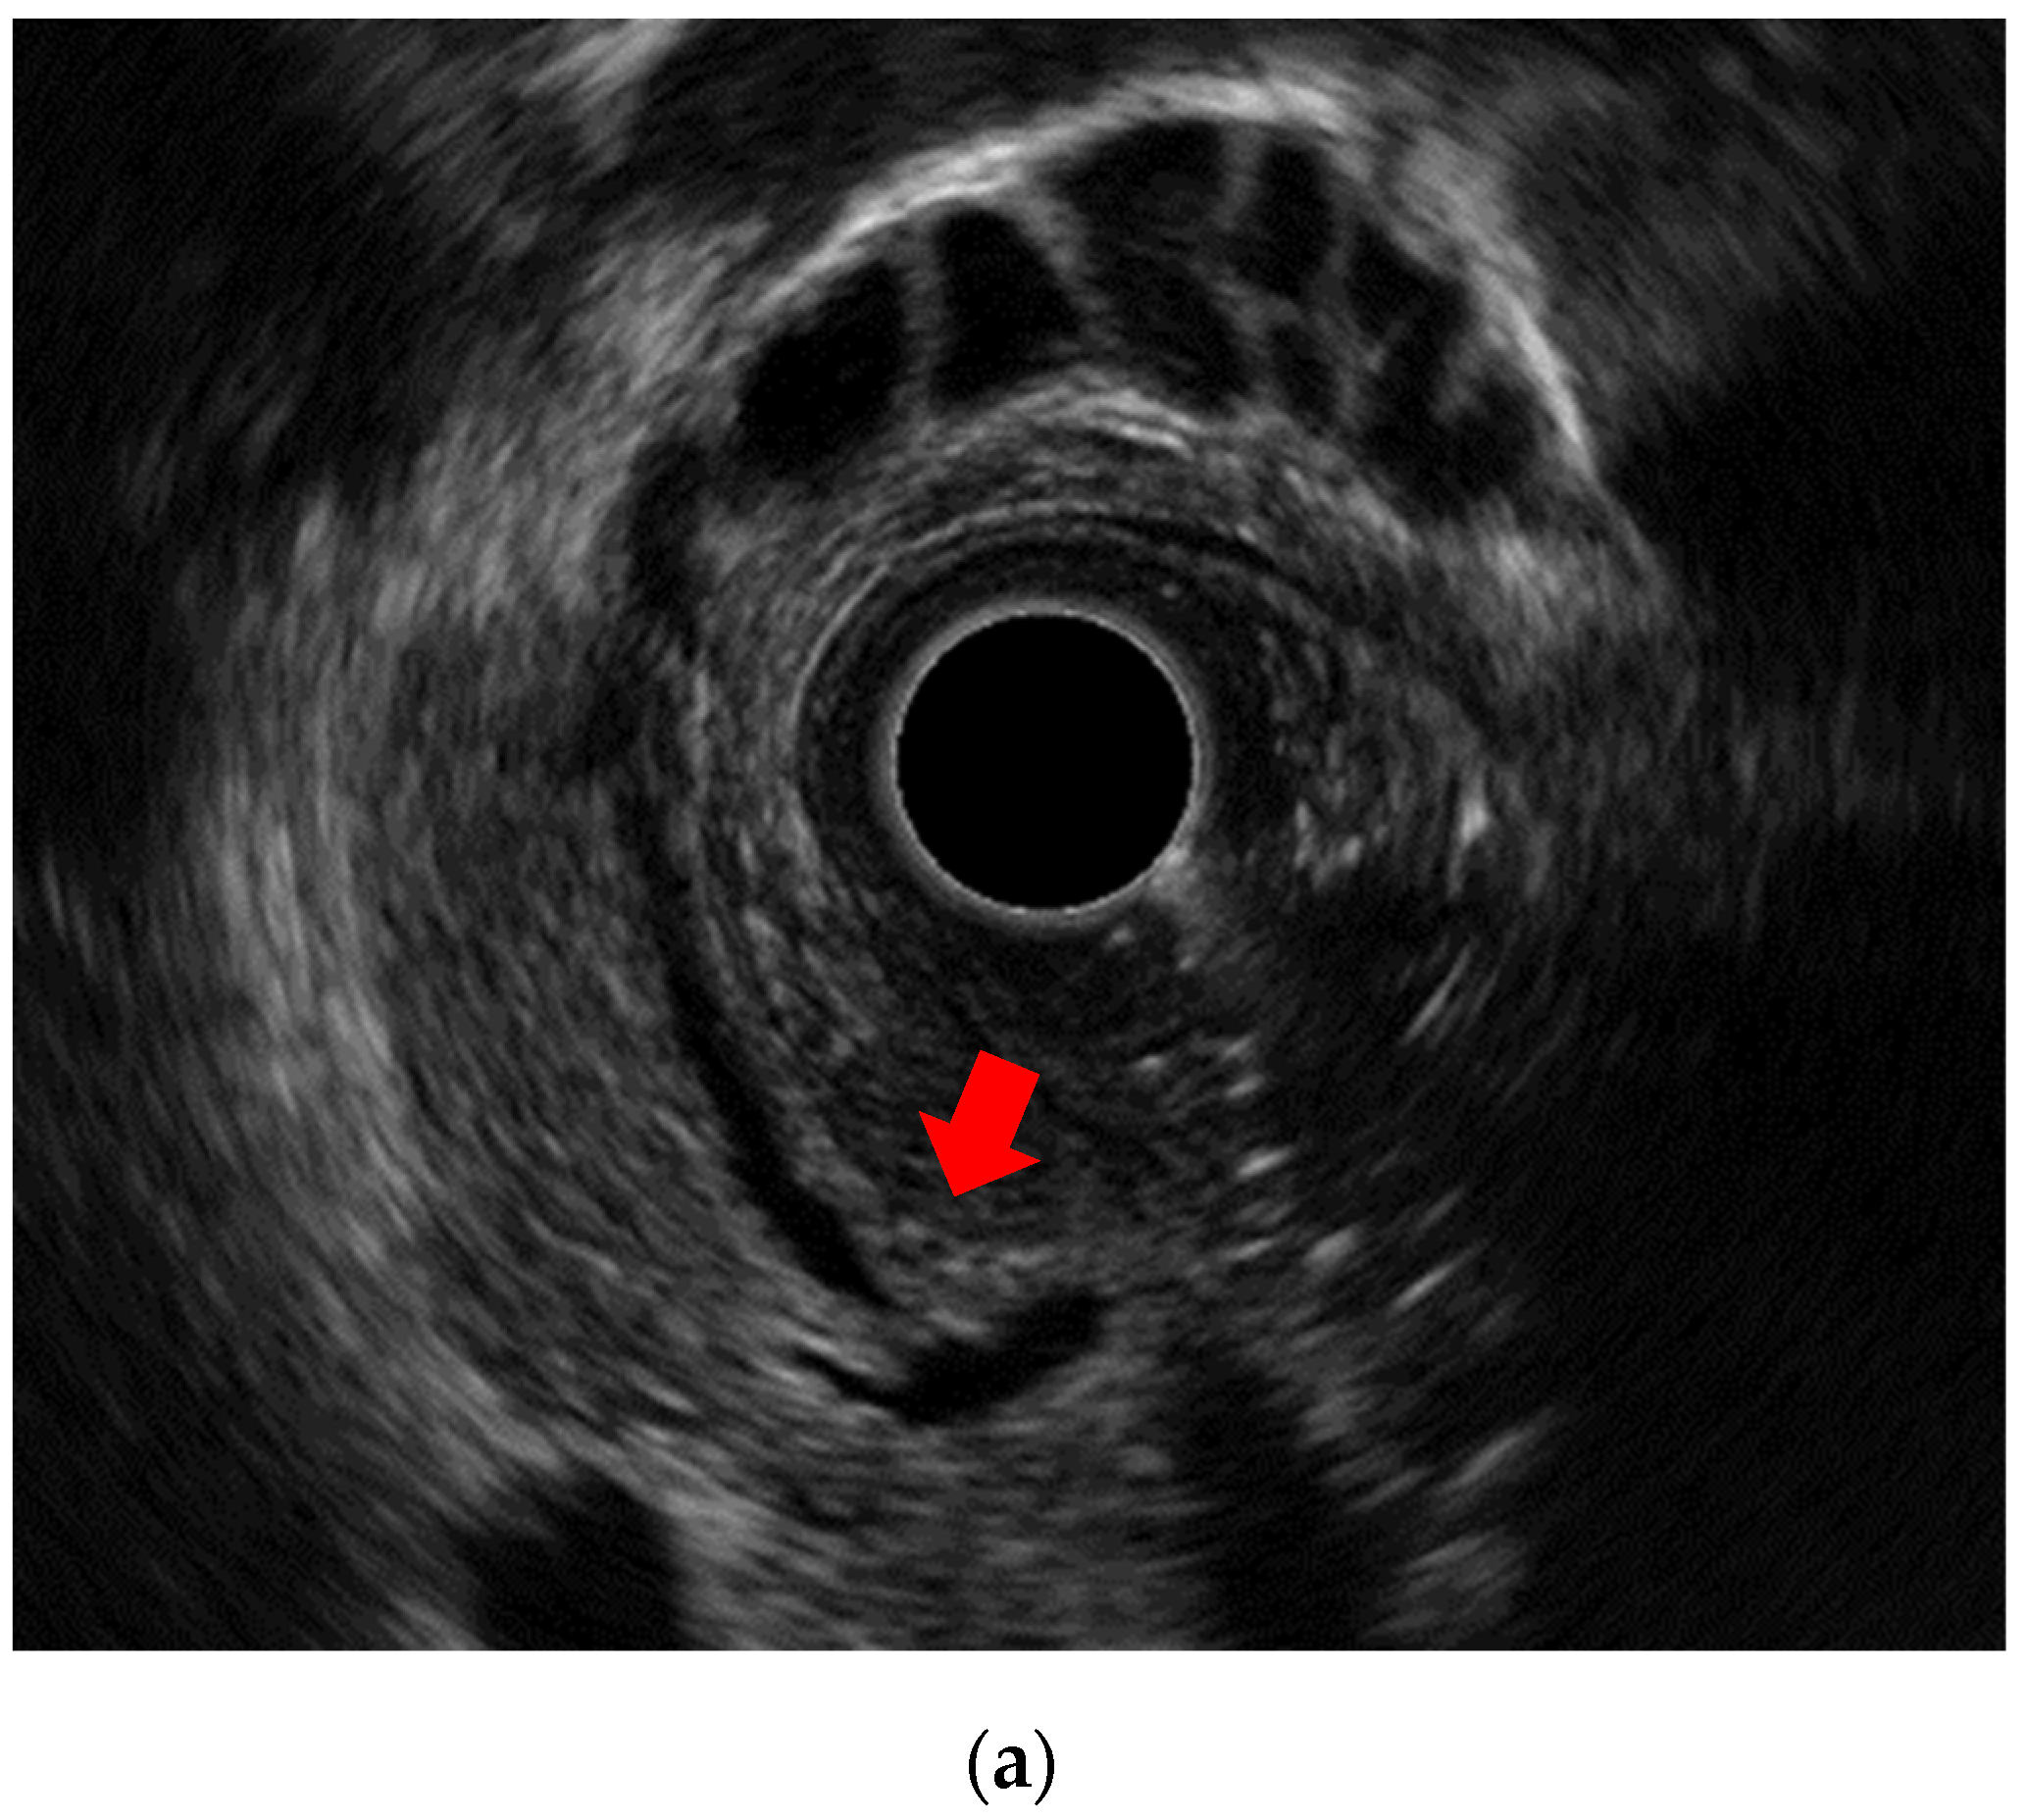

Figure 3. Detection of small choledocholithiasis by intraductal ultrasound (IDUS) and endoscopic ultrasound (EUS): (a) IDUS image of choledocholithiasis (arrow, 5 mm); (b) EUS image of choledocholithiasis (arrow head, 5 mm).

IDUS is also known to be effective for detecting choledocholithiasis; Linghu et al. [18] reported that its accuracy and sensitivity in the diagnosis of extrahepatic bile duct stones were both 100%. Another study reported [19] that IDUS revealed residual stones in 38% of cases despite a normal cholangiography. Whether IDUS should be performed to confirm residual stones as a routine procedure is not clearly defined, and further investigation is needed.